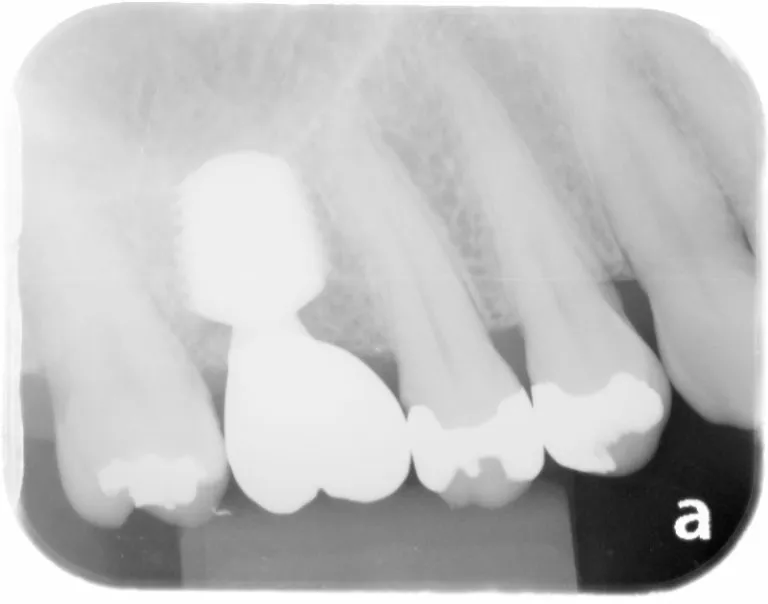

【症例6】

レントゲン写真

治療名

インプラント治療

治療説明

治療期間

約3ヶ月

副作用・リスク

手術中に神経や血管を傷付ける可能性があります。痛み、腫れ、出血がありますまた、インプラントの初期固定が取れない場合、治療期間が長引いたり、すぐに仮歯を装着できない場合があります。

料金

¥495,000(税込)